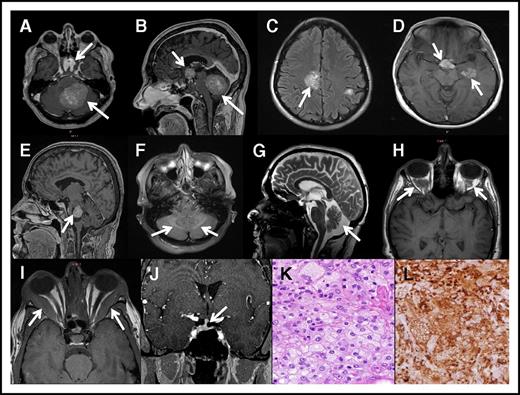

Neurologic signs or symptoms were present in 92% of patients (15% presented with a neurologic complaint) and 87% (55 patients) had an abnormal head MRI. Clinical involvement included mild cognitive impairment (40%) or dementia (8%), brainstem findings (52%), cerebellar ataxia (40%), sensorineural hearing loss (8%), seizures (8%), headaches (23%), and peripheral neuropathy (56%). The most prominent bulbar symptoms were diplopia (15%), dysarthria (14%), and dysphagia (13%). Neuroradiologic features included atrophy in 30% of patients (Figure 3G), cerebral masses in 20%, cerebellar masses in 16% (Figure 3A-E), retro-orbital masses in 27% (Figure 3H), and dural thickening in 7%. A small number of cases had infiltrative T2-weighted fluid attenuated inversion recovery lesions (Figure 3F) and extraocular muscle thickening (Figure 3I). Periorbital masses were frequently space occupying and caused visual impairment (15 cases), gaze palsies (9 cases), proptosis (3 cases), and papilledema (1 case). Pituitary abnormalities included pituitary stalk thickening in 14 cases (Figure 3J), T2 hypointensities in 7 cases, and suprasellar masses in 5 cases. Brain mass pathology revealed foamy macrophages (Figure 3K-L). Overall, neurologic disease in ECD was more prevalent than previously reported,3,4,7,8,27 and we have expanded its spectrum to involve neurodegeneration, seizures, dural and white matter nondisplacing lesions, and extracranial space-occupying lesions.

Brain images in ECD. (A) Axial post contrast brain MRI showing suprasellar and cerebellar involvement in a patient with ECD. (B) Sagittal post contrast brain MRI (from panel A) showing suprasellar and cerebellar tumors in a patient with ECD. (C) Axial fluid attenuated inversion recovery brain MRI showing ECD tumors in cerebral hemispheres. (D) Axial fluid attenuated inversion recovery brain MRI showing ECD tumors in cerebral hemisphere. (E) Sagittal post contrast brain MRI showing an ECD tumor with cystic components in the midbrain-pons of a patient with ECD. (F) T2 fluid attenuated inversion recovery MRI image showing increased symmetrical signal intensity in the cerebellum. (G) Neurodegeneration and atrophy of the cerebellum in a patient with ECD seen on brain MRI. (H) Orbital involvement with tissue accumulation in the intraconal space secondary to histiocytes accumulation in ECD. (I) Orbital involvement showing increased thickening of the lateral rectus muscle. (J) Pituitary stalk is thickened secondary to macrophage accumulation in ECD and deviated to the right. (K) Hematoxylin and eosin stain for brain lesion showing foamy macrophages and inflammation in brain mass biopsy specimen (original magnification ×40). (L) CD68 KP-1 stain of panel K highlighting the foamy macrophages (original magnification ×40).